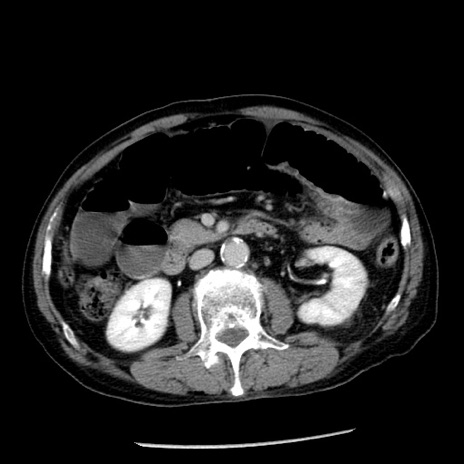

症例26(横断像)

【症例】80歳代男性

【主訴】嘔吐

【現病歴】昨晩2回嘔吐あり、今朝になっても嘔吐あり。来院。

【既往歴】胃潰瘍

【身体所見】意識清明、BT 37.6℃、BP 166/95mmHg、HR 100bpm、SpO2 97%、腹部:平坦・軟、腸蠕動音聴取良好、圧痛なし。

【データ】WBC 21900、CRP 1.46